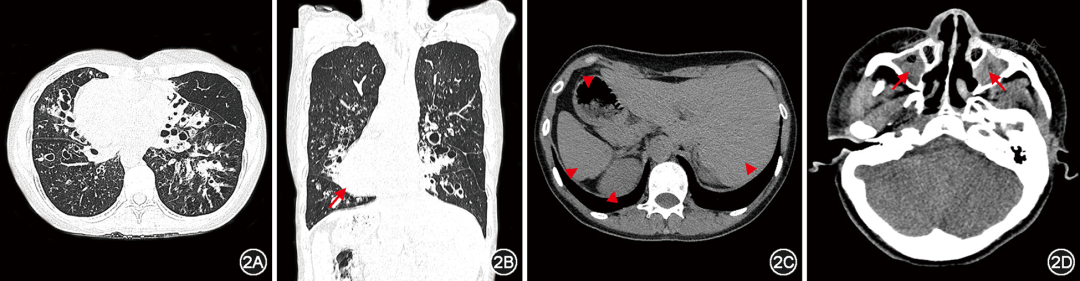

纤毛功能障碍累及多个器官,影像学检查应重点关注肺部、鼻窦、心脏和腹腔脏器等器官的表现。几乎所有的成人PCD胸部高分辨率CT(high resolution CT,HRCT)均显示出一定程度的支扩,病变主要分布在右中叶和左舌叶,其次为下叶,而上叶较少受累(图2)。肺部的其他影像学特征还包括肺叶或肺段不张、黏液栓塞等,一般较少出现肺气肿和肺大疱。鼻窦CT可评估PCD患者是否存在鼻窦炎或鼻息肉。超声检查是评估心脏和腹腔脏器常用的检测手段,有助于评估PCD患者的内脏位置及是否合并先天性心脏病。内脏位置的评估与判断对于患者以后可能的急性创伤评估或急诊手术时内脏器官的定位具有重要参考意义。

图2  典型原发性纤毛运动障碍患者CT所见

注:患者女,28岁,DNAH5双等位致病变异,胸部CT示右肺中叶、左舌叶及双肺下叶多发囊状支气管扩张,伴部分支气管管壁增厚、黏液栓塞,可见全内脏反位,长箭头示右位心,三角箭头示腹腔内脏全反位(胃、肝脏、脾脏、肾脏)(图2A~2C);鼻窦CT示双侧上颌窦黏膜增厚,窦腔见软组织密度灶填充,红色箭头示慢性鼻窦炎(图2D)。